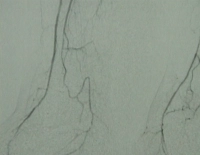

Filmbeispiel: TASC D → offene Rekonstruktion

AVK Stadium IV rechtes Bein, Stadium III linkes Bein mit:

- hochgradiger Arteriosklerose der terminalen Aorta und Beckenstrombahn bds.

- langstreckigem Verschluss der A. femoralis superficialis bds.

- Teilverschlüssen der Unterschenkelarterien bds.

Präoperative DSA des Patienten: